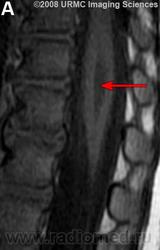

МРТ.  Терминальный желудочек

http://www.radsource.us/clinic/0807